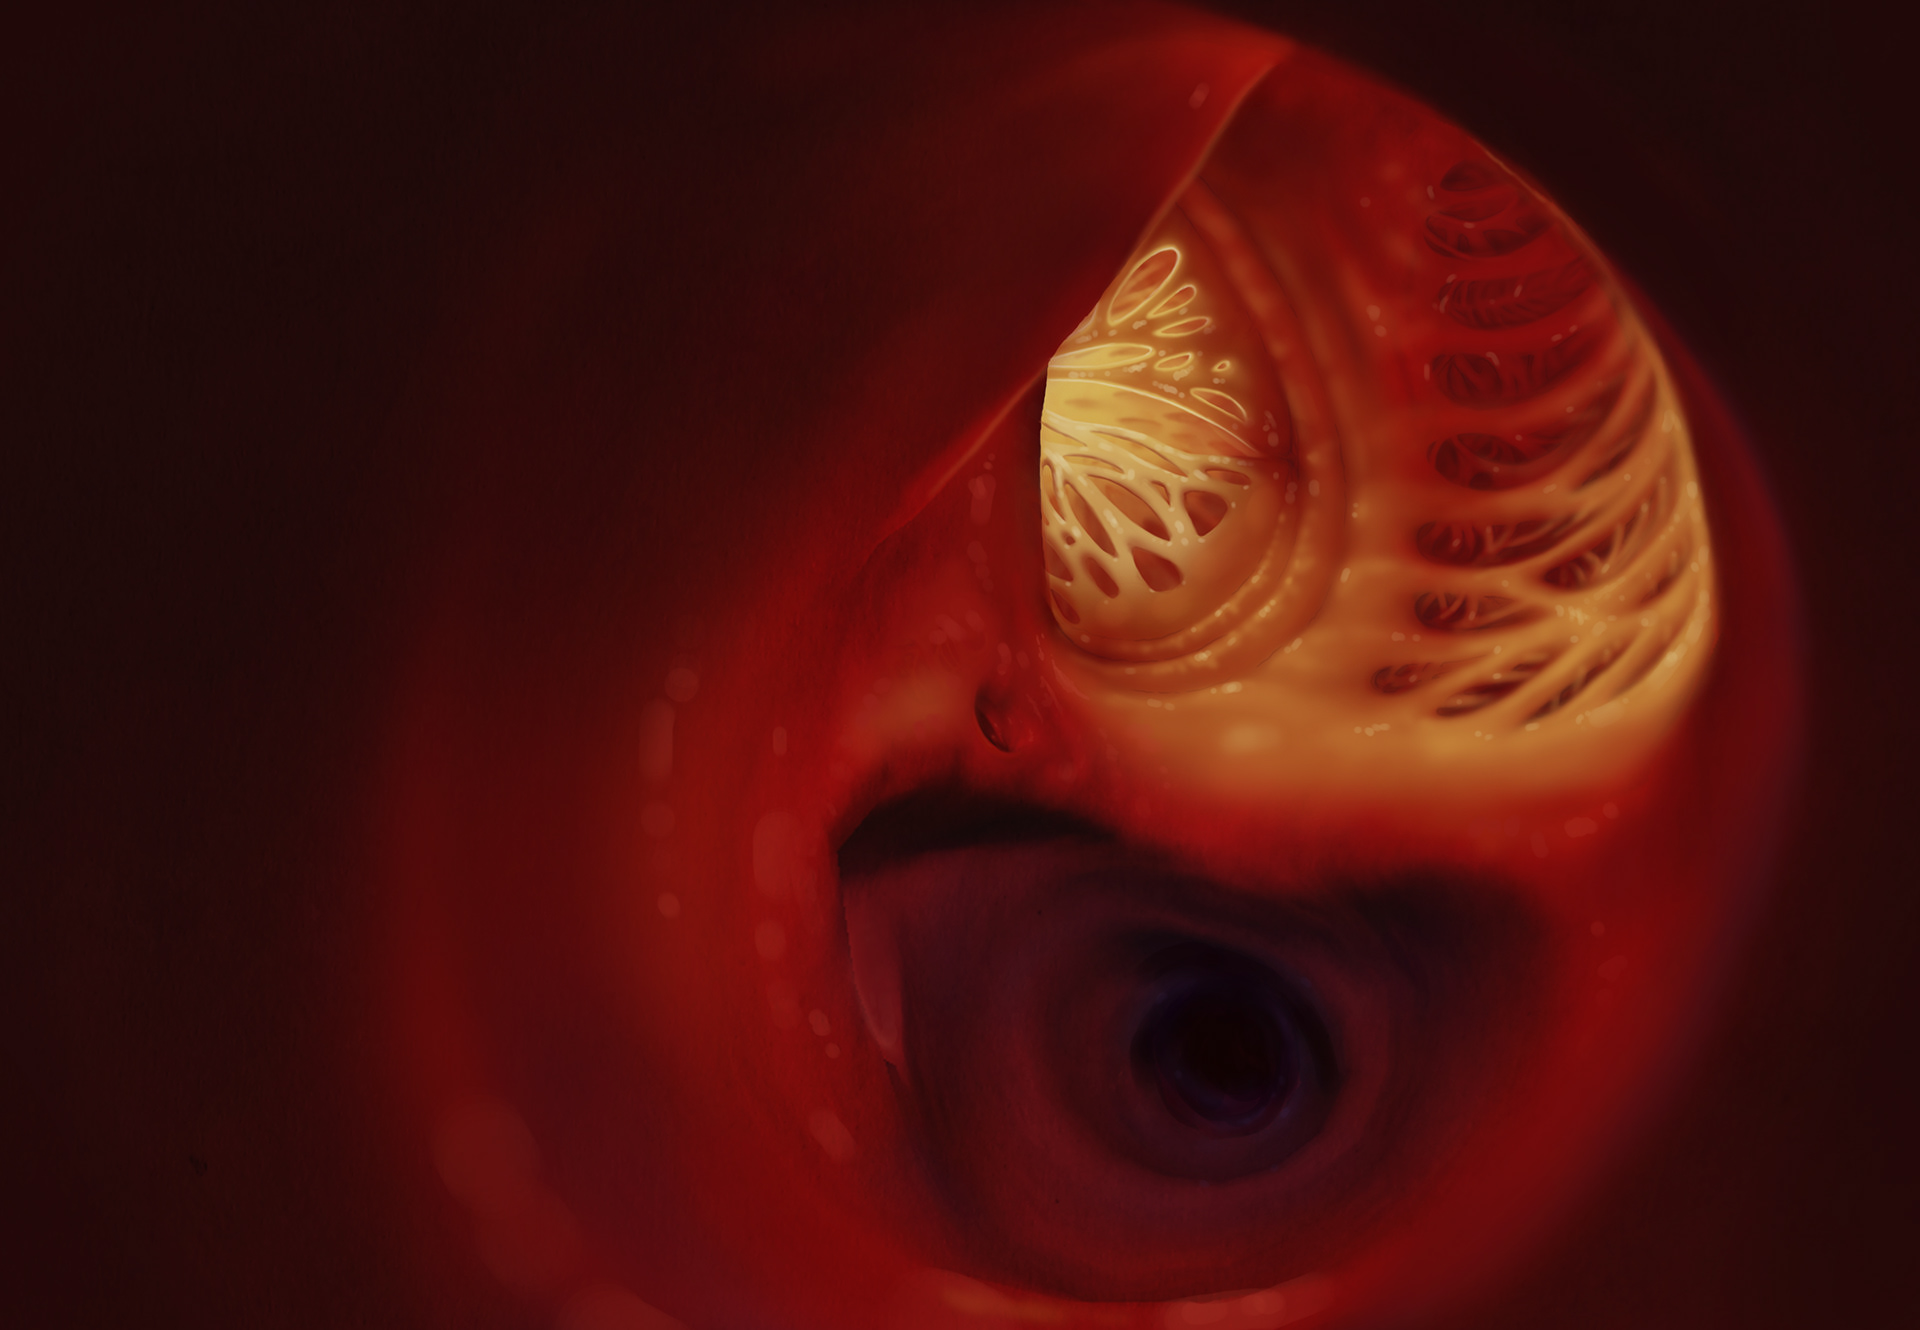

This shows the progression of what Aortic Valve Stenosis looks like.